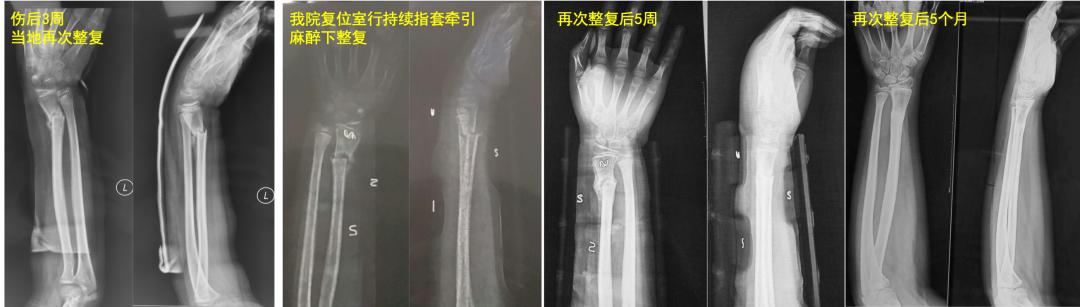

老师: 下面两个病例,分别是9岁4个月男孩的前臂中段骨折,保守治疗后3个月骨折对位、愈合良好。另外一个12岁男孩,早期外院保守治疗,三周时骨折再移位,于我院再次整复后恢复满意。